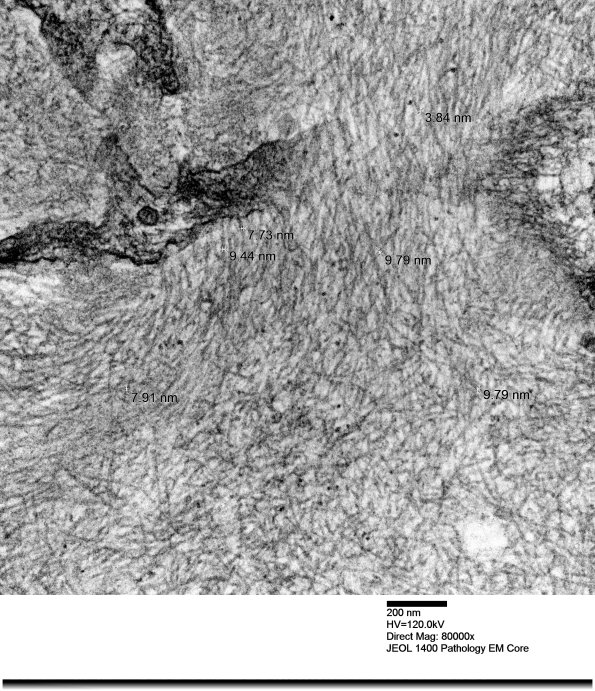

Amyloid deposition in the kidney. At higher magnification the amyloid width is 9-10nm. (electron micrograph)